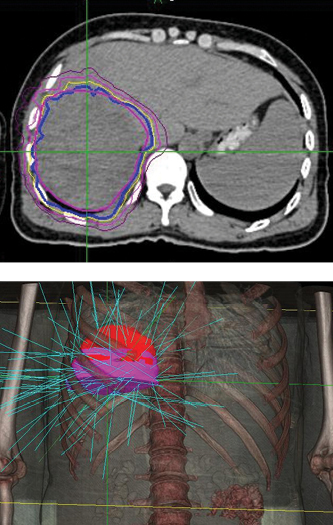

A 42-year-old male with chronic hepatitis B was initially diagnosed with primary liver cancer. He received radiofrequency ablation. Then an MRI revealed recurrence in front of the original lesion. The patient underwent interventional therapy in March 2012, but was hospitalized a month later when a CT showed a residual tumor and acute cholecystitis. Diagnosis was hepatocellular carcinoma, T2N0M0, Stage II. The patient was treated with the CyberKnife® System at 302 Hospital of PLA.

The initial follow-up took place four months after treatment, and CT showed no residual tumor. At the eight-month follow-up, MRI examination showed a region of necrosis in the location of the right lobe tumor. At 32 months post treatment an MRI showed no residual disease or any late toxicities.

“The CyberKnife System’s ability to track and adjust the beam with fiducials is key to giving high-dose SBRT to the liver.”

– Li Yu, M.D., Chairman, Radiation Oncology, 302 Hospital of PLA